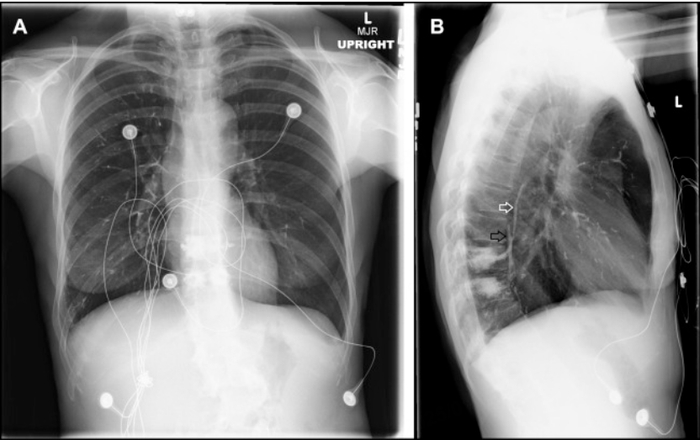

在急诊科,患者接受了全面的体格检查,结果未见异常。心电图检查和基础实验室检查结果也未见显著异常。为了进一步评估,进行了胸部X线检查。

患者胸部X线的后前位片显示双侧肺部有多发管状、分支状放射性不透明影(图2A)。侧位片进一步显示这些不透明影延伸至前外静脉丛和奇静脉(图2B)。

第二位患者,侧位片明显发现不透明影走向,在排除其他可能胸痛病因后,最终确诊为肺水泥肺栓塞。肺水泥肺栓塞是经皮椎体成形术的已知并发症,因聚甲基丙烯酸甲酯泄漏至系统静脉而发生。此过程通常始于前外静脉丛,进而进入奇静脉、下腔静脉、右心房,最终到达肺血管床,与本患者影像表现高度一致。